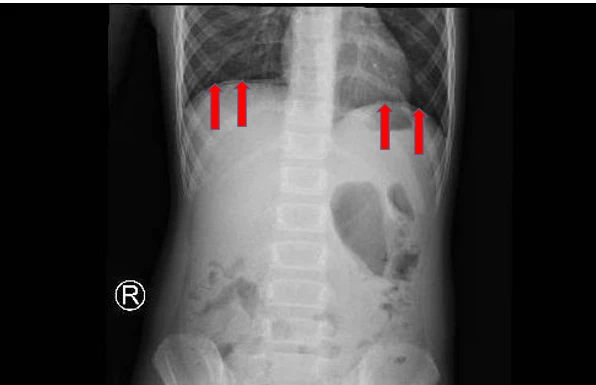

Kết quả chụp X-quang bụng có hơi tự do trong ổ bụng. Xét nghiệm máu có bạch cầu tăng, rối loạn điện giải.